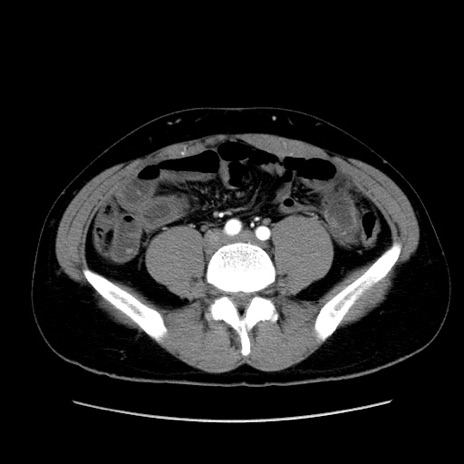

症例36(横断像)

【症例】20歳代 男性

【主訴】心窩部痛

【現病歴】今朝より上腹部痛あり。一旦軽快していたが再度出現したため救急要請。昨日夕に白身の魚を含む刺身を食べた。

【身体所見】BP 136/89mmHg、HR 74/min、BT 37.0℃、腹部:膨満、軟、心窩部に圧痛あり。反跳痛なし、筋性防御なし、腸雑音やや亢進あり。

【データ】WBC 17700、CRP 0.48